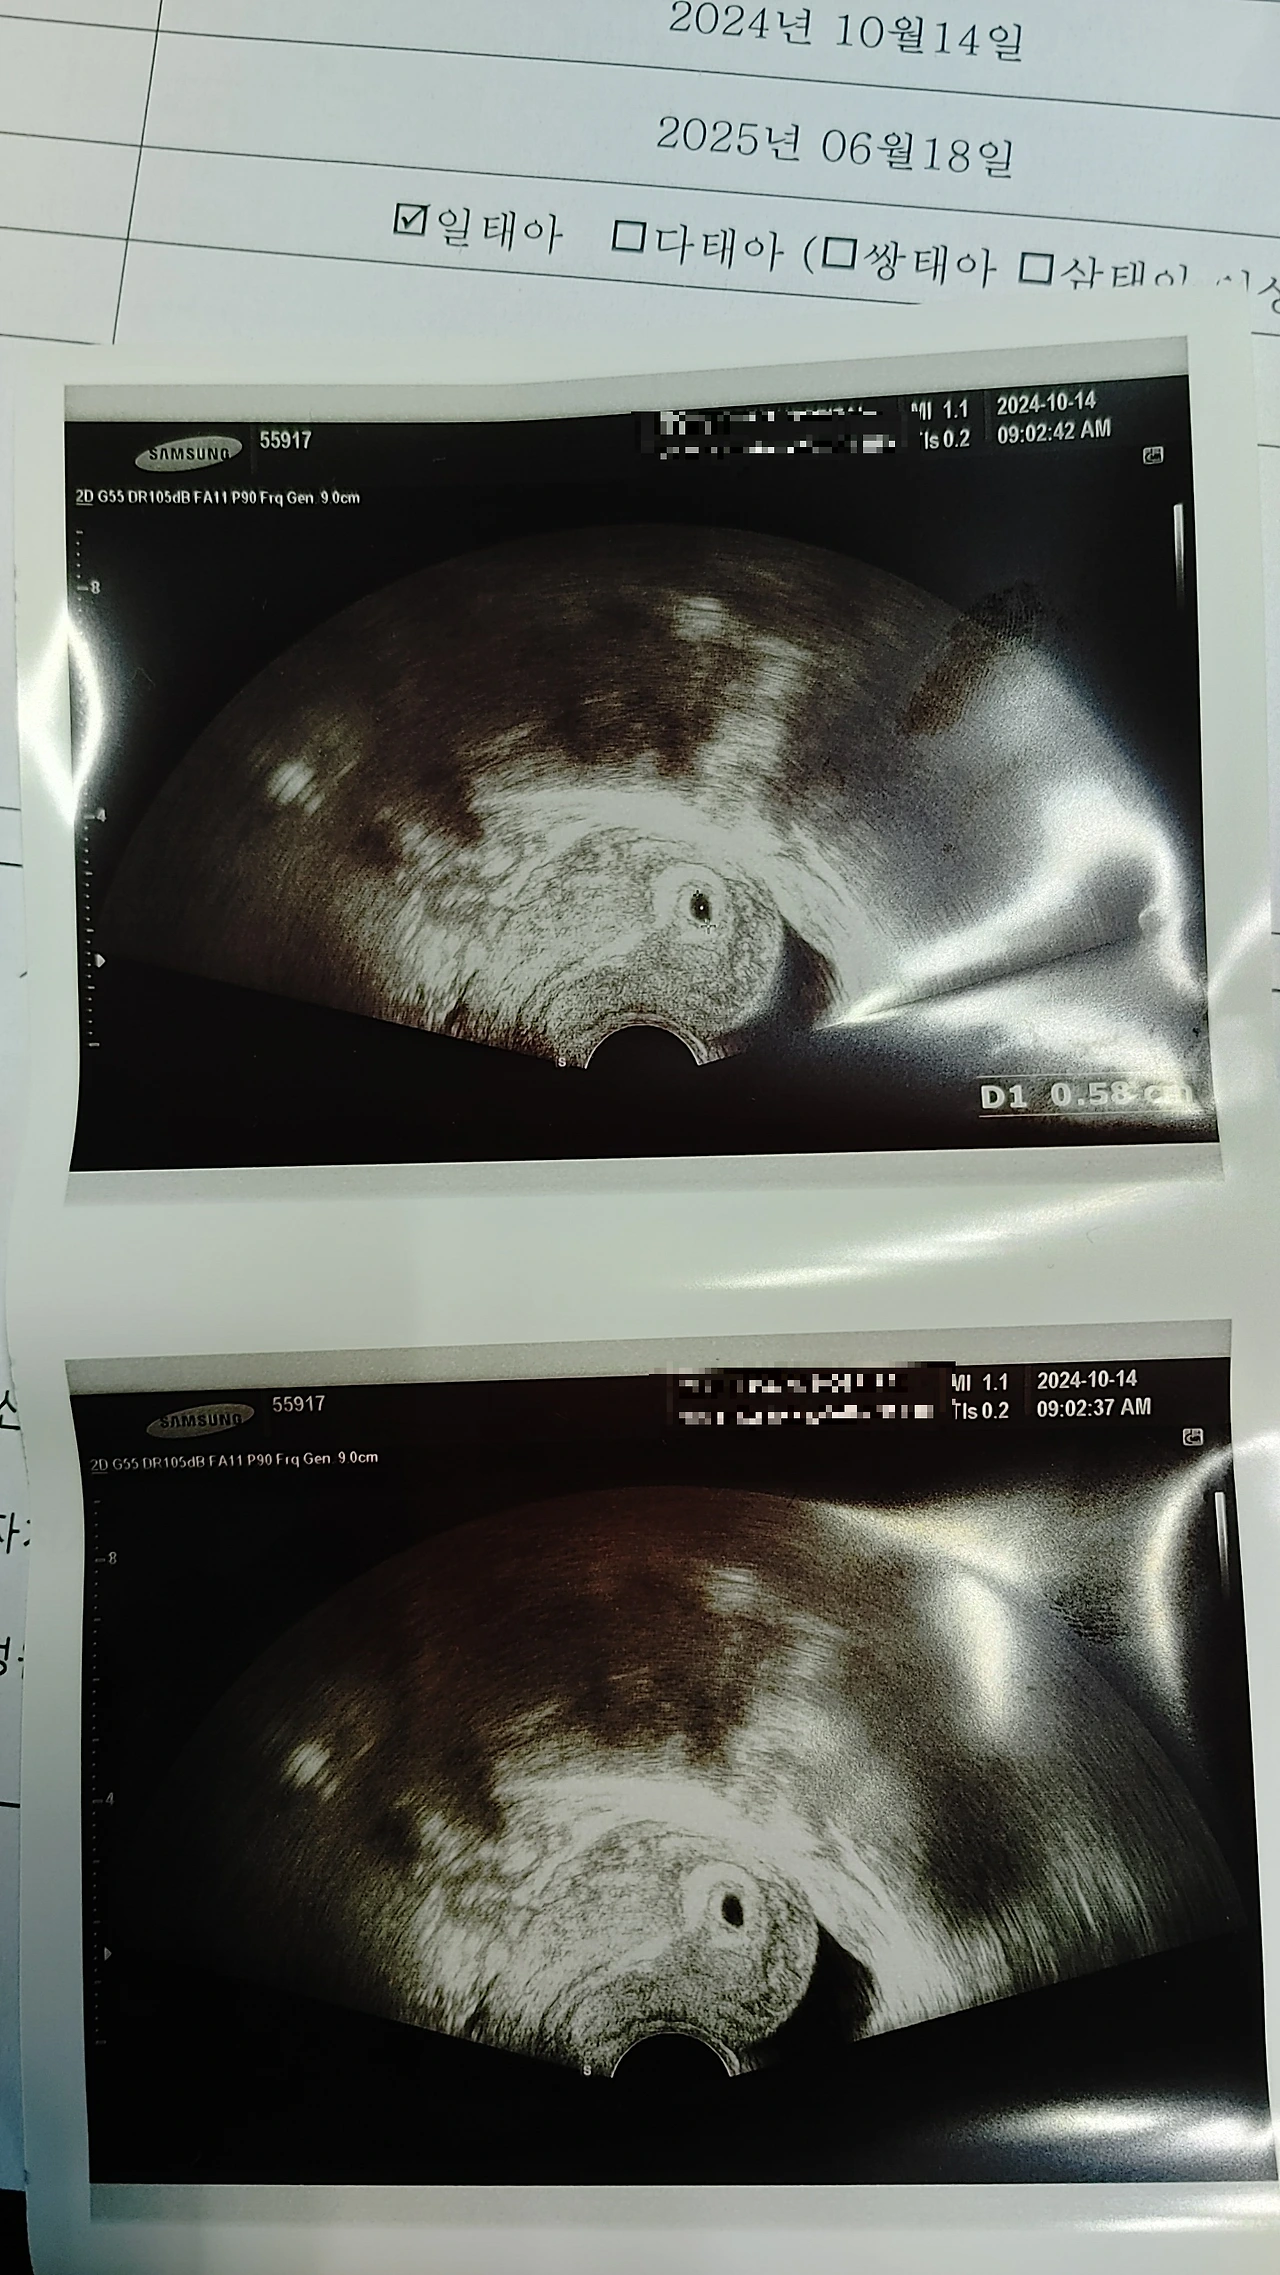

대학원 2학기로 바쁜 나날을 보내던 시월의 어느날, 우리는 기쁜 소식을 접했다.

1트만에 엄마 뱃속에 딱하니 바로 붙어버린 이녀석, 대견하다.